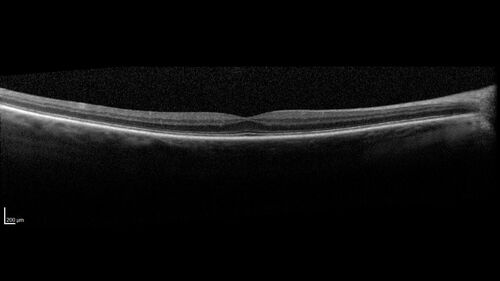

BRVO with good vision

87 year old man with good vision (diabetes without retinopathy). VA 20/25 OU. Vision never worsened from BRVO OS.